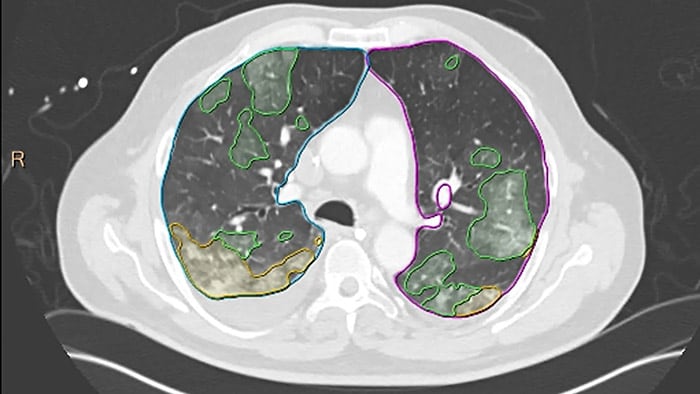

“The immediate and complex long-term needs of COVID-19 patients, combined with the growth of elective care, has highlighted the continued need for advanced fully-integrated radiology solutions that support efficient diagnosis, follow-up and communication across multiple clinical domains,” said Calum Cunningham, General Manager of Enterprise Diagnostic Informatics at Philips. “The new generation of IntelliSpace Portal adds numerous AI-enabled features that automatically generate quantitative measurements, simplify workflows, and make radiology data available anywhere it’s clinically relevant in an organization.” Expanding its ecosystem for radiology solutions, new clinical software packages [1] in cardiology, pulmonology, oncology and neurology being launched with IntelliSpace Portal 12, several of which have been integrated in collaboration with Pie Medical Imaging BV or Riverain Technologies, include: MR Cardiac Analysis – Pre-processing images to deliver AI-based right ventricle and left ventricle segmentation to ensure accurate volumetric and functional measurements, enabling completion of a full cardiac MRI functional analysis in less than 5 minutes [2]. MR Caas™ 4D Flow Analysis – To reduce analysis time and improve reliability of valvular flow quantification [3], Caas [4] MR 4D Flow visualizes and quantifies blood flow patterns in a patient’s heart and main arteries. Pulmonology CT Pulmo Auto Results [5] – Featuring AI algorithms trained on complex pulmonary CT scans, including those of COVID-19 patients, CT Pulmo Auto Results software performs automatic lung segmentation and lesion segmentation, together with classification of ground glass opacities/consolidation. Its automatically generated reports include volume summaries and lesion distribution data to help in the quantitative assessment of pulmonary infiltrates, enhancing diagnostic confidence without increasing reading time. Oncology CT ClearRead™ CAD Lung Nodule Analysis [6] – featuring AI-based detection and characterization for various nodule types including solid, part-solid and ground-glass lung nodules, enabling to perform nodule searches 26% faster and detect 29% of previously missed nodules [7]. Neurology CT Brain Perfusion Analysis – IntelliSpace Portal 12 now supports automatic brain perfusion measurements instantly available on PACS with the option of automatically emailing perfusion results to a stroke patient’s clinicians within two minutes to reduce door-to-needle time. Additional Enhancements The software also includes a new photorealistic volume rendering [8] technology using an interactive virtual light source to improve the visualization of volumes in terms of their depth and relationship to other key anatomies – enhancing its use as an educational and communication tool. Other enhancements in IntelliSpace Portal include workflow innovations for vascular analysis to deliver faster results, new automatic lesion segmentation propagation between time-points for longitudinal tumor tracking, new CaasTM [4] myocardial strain quantification software, and enhanced automatic capabilities for CT coronaries analysis.